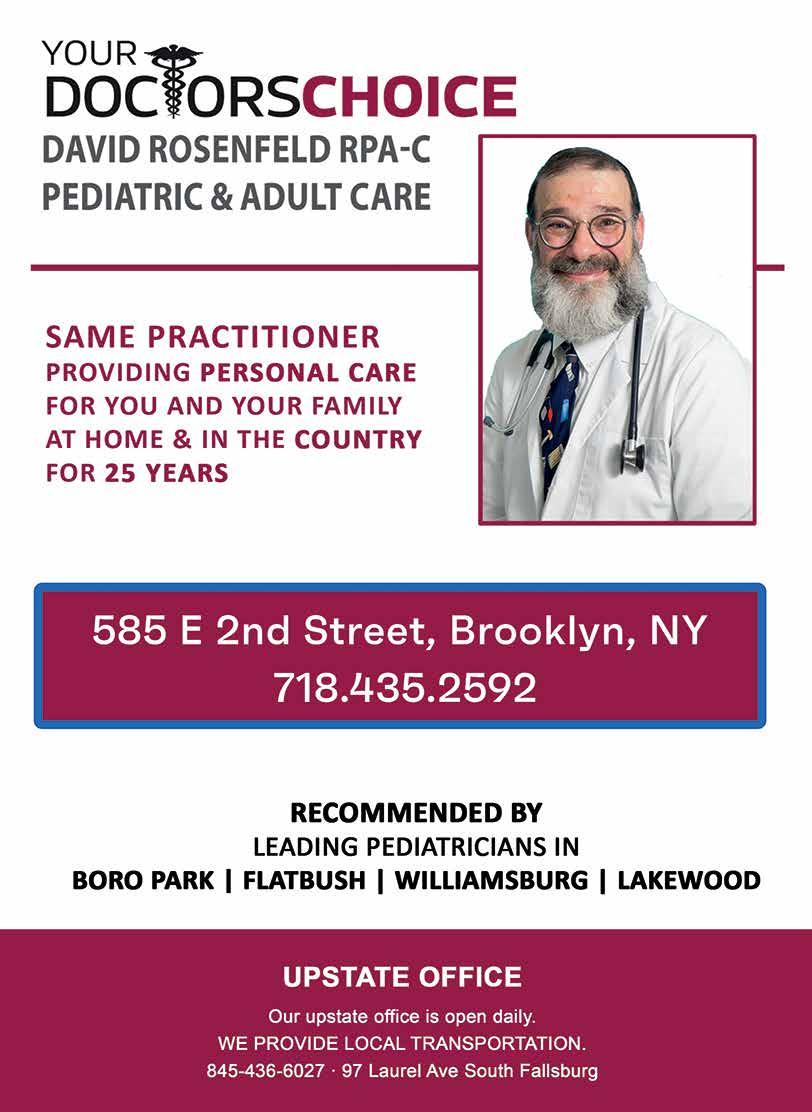

First, let's briefly talk about the flu itself. The flu affects between 500,000 and 1 million people in the United States annually and causes approximately 25,000 to 30,000 deaths. The flu is a respiratory virus that can cause respiratory complications, as well as pneumonia,

Now that the flu season is coming, can you please explain what the flu shot is, who should get it, whether it’s possible to catch the flu after getting vaccinated, if it’s really worth taking, whether there are some people for whom it might not be worth getting, and what the common side effects might be?

vaccine conversation for the purpose of this article and focus on the specific questions asked.

Some of the common concerns people have about the vaccine are egg allergies, mercury-containing preservatives used in the vaccine, the effectiveness of the vaccine, and the possibility of getting the flu from the vaccine.

health

As far as egg allergies and mercury in the vaccine, there are forms of the vaccine easily available that have no preservatives or eggs. Although some people may feel a bit flu-like for a day or two after getting the vaccine, this is not the actual virus and tends to be mild and relatively short compared to the actual flu virus. Other common side effects of the vaccine are injection site redness and pain that usually last a day or two.

As far as the effectiveness of the vaccine, there are studies done yearly to measure the effectiveness of the vaccine, and it ranges most years between 30 and 60 percent, with a low of 19 percent in 2014 and 56 percent in 2024.

Although people may get the flu even after being vaccinated, they will usually have a more mild case. As with everything else, discuss your individual concerns with your medical provider and have a safe, warm winter.